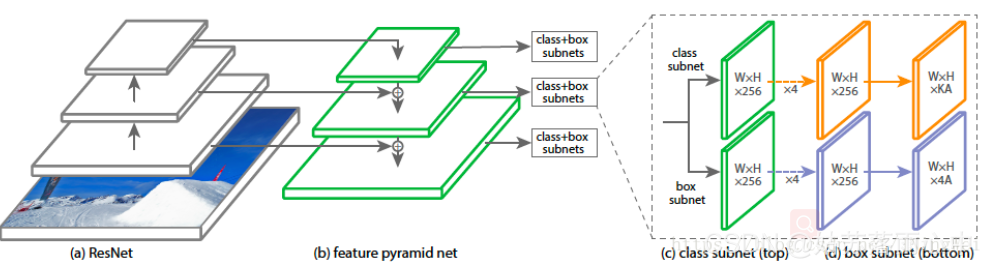

RetinaNet的框架整体是ResNet+FPN+FCN,它使用ResNet作为backbone来提取图像特征,然后从中抽取5层特征层来构建特征金字塔网络(FPN: feature pyramid network),最后接两个独立的**全卷积网络(FCN: full convolution network)**分别得到物体的类别信息和位置框信息。

对于RetinaNet的网络结构,有以下5个细节:

- 在Backbone部分,RetinaNet利用ResNet与FPN构建了一个多尺度特征的特征金字塔。

- RetinaNet使用了类似于Anchor的预选框,在每一个金字塔层,使用了9个大小不同的预选框。

- 分类子网络:分类子网络为每一个预选框预测其类别,因此其输出特征大小为KA×W×H, A默认为9, K代表类别数。中间使用全卷积网络与ReLU激活函数,最后利用Sigmoid函数输出预测值。

- 回归子网络:回归子网络与分类子网络平行,预测每一个预选框的偏移量,最终输出特征大小为4A×W×W。与当前主流工作不同的是,两个子网络没有权重的共享。